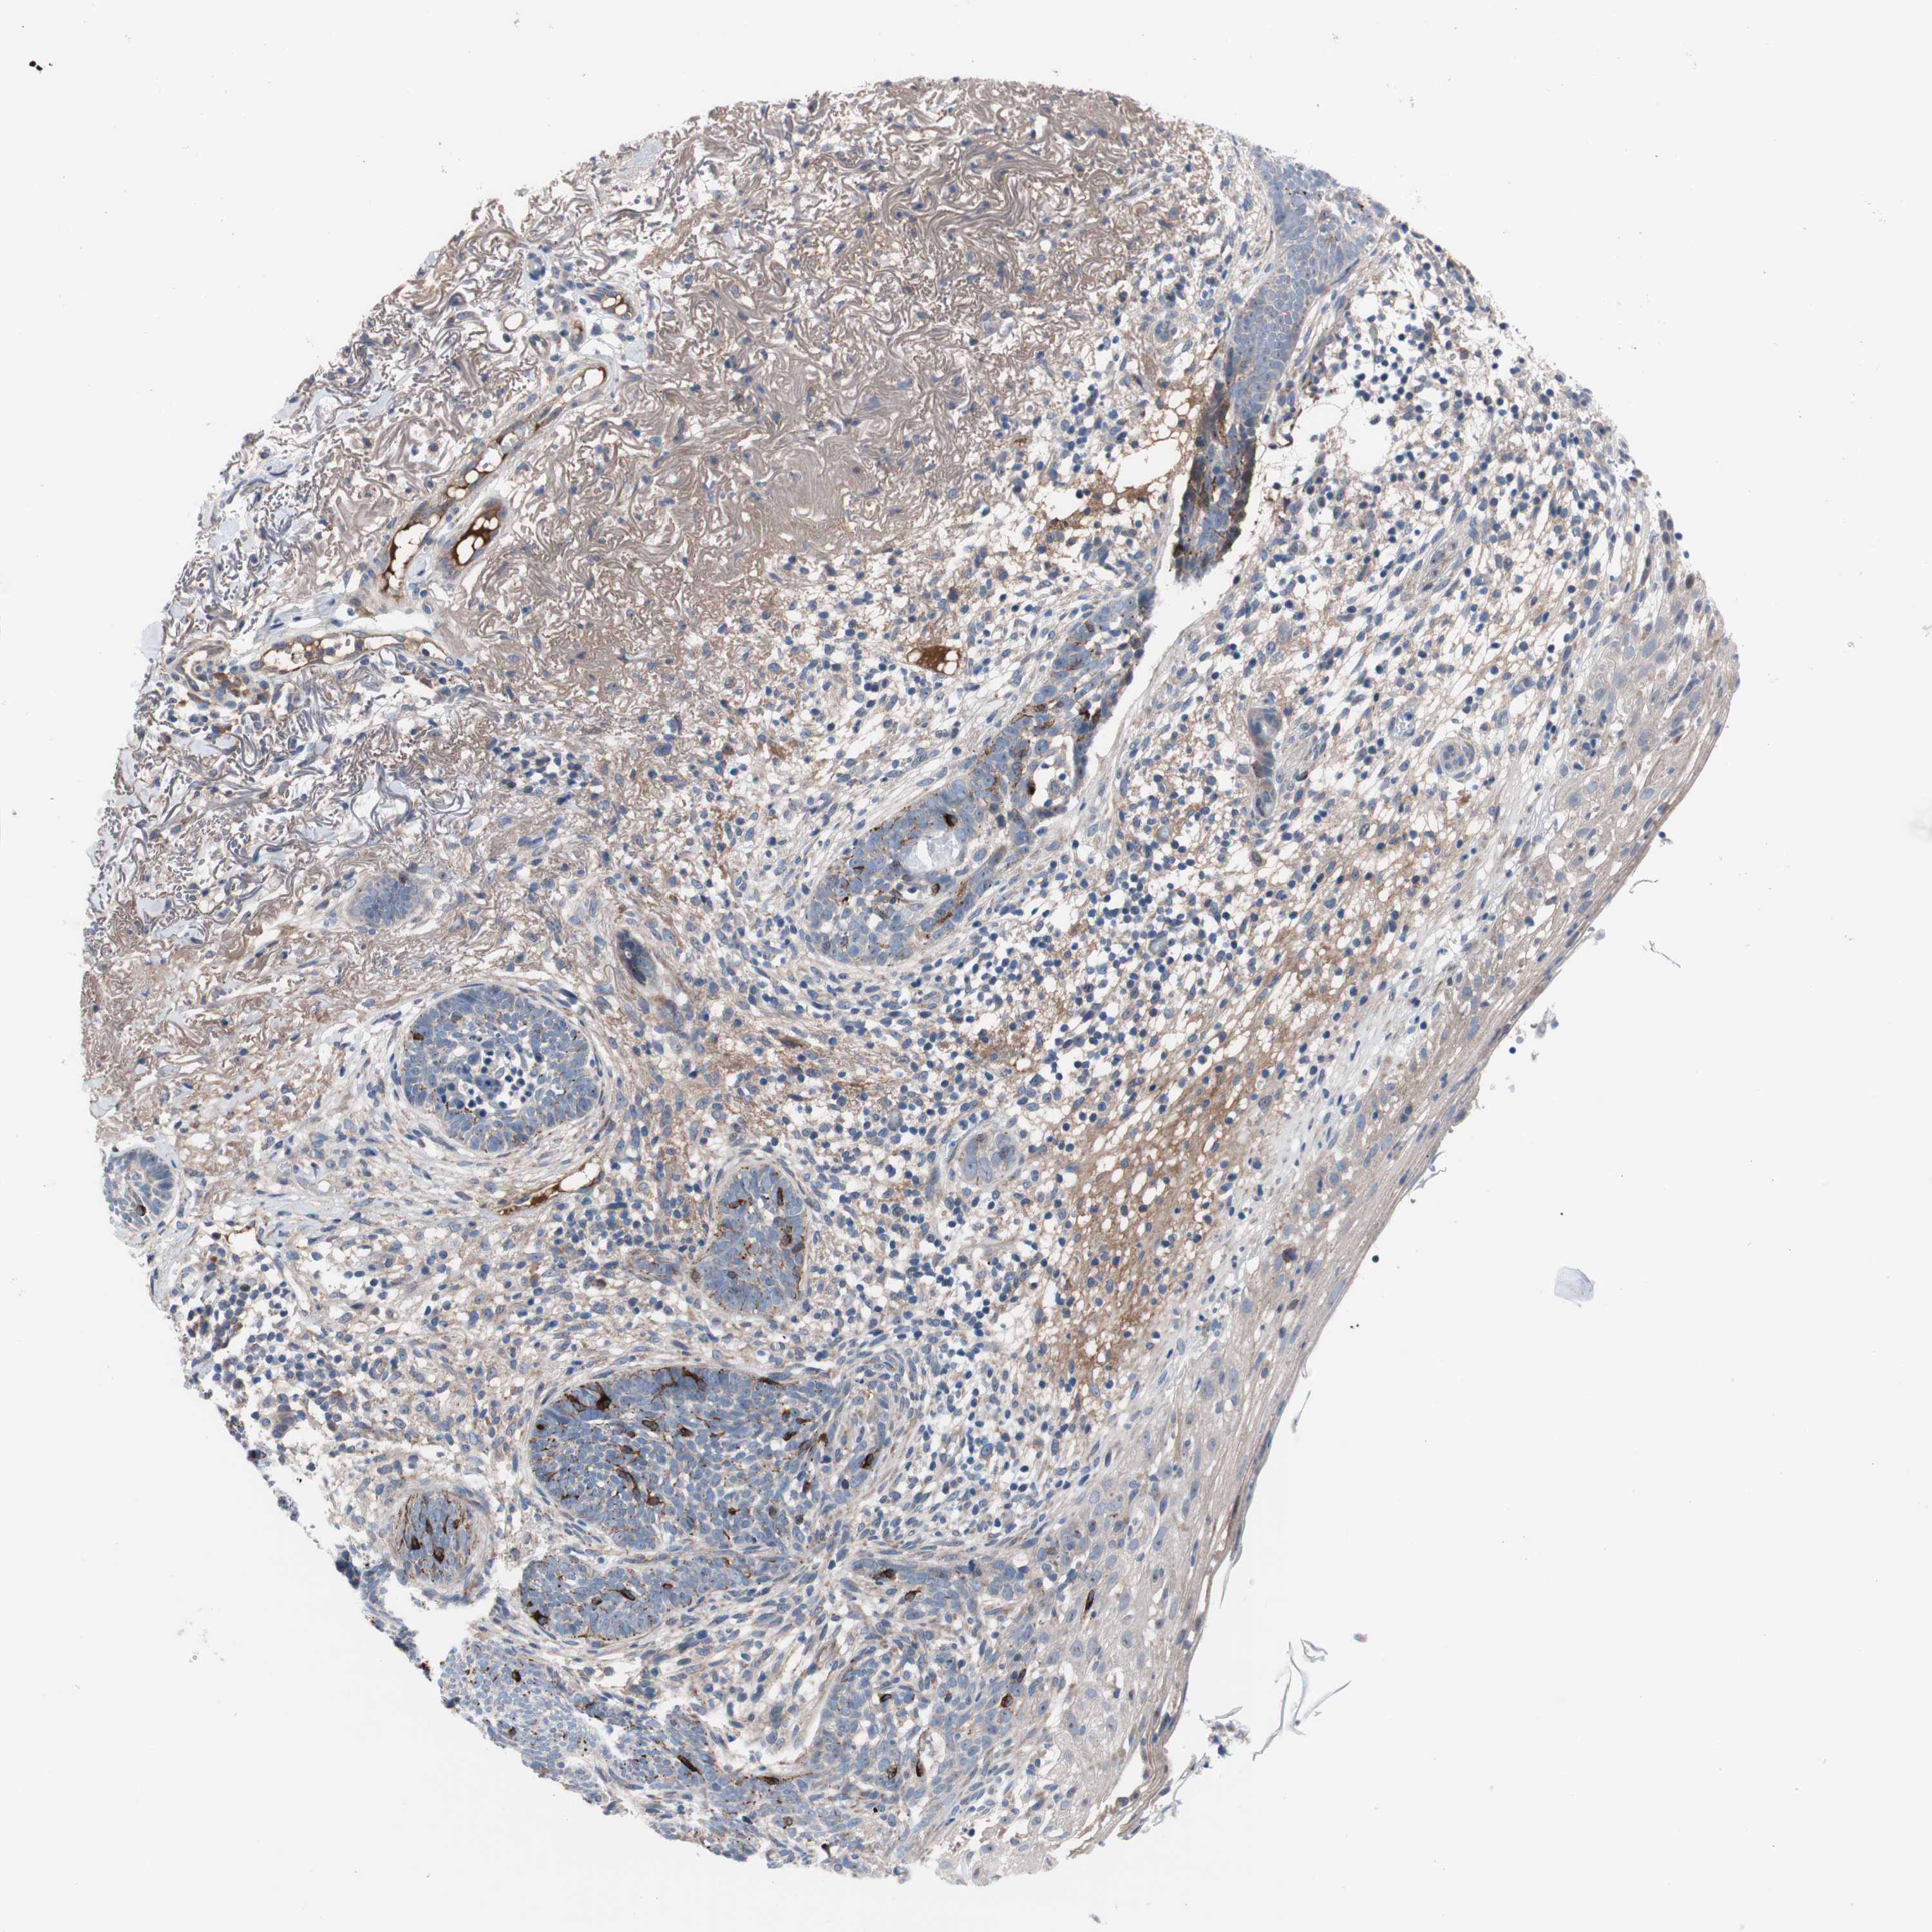

SKIN CANCER - Protein expressioni

A mouse-over function shows sample information and annotation data. Click on an image to view it in a full screen mode. Samples can be filtered based on level of antibody staining by selecting one or several of the following categories: high, medium, low and not detected. The assay and annotation is described here.

Antibody staining in the annotated cell types in the current human tissue is reported as not detected, low, medium, or high, based on conventional immunohistochemistry profiling in selected tissues. This score is based on the combination of the staining intensity and fraction of stained cells.

Each image is clickable and will lead to virtual microscopy that enables deeper exploration of all samples and also displays staining intensity scores, fraction scores and subcellular localization as well as patient and tissue information for each sample.

Antibody HPA006874

Antibody HPA007208

Staining

High

Medium

Low

Not detected

Intensity

Strong

Moderate

Weak

Negative

Quantity

>75%

75%-25%

<25%

None

Location

Nuclear

Cytoplasmic/membranous

Cytoplasmic/membranous,nuclear

Squamous cell carcinoma, NOS

Basal cell carcinoma